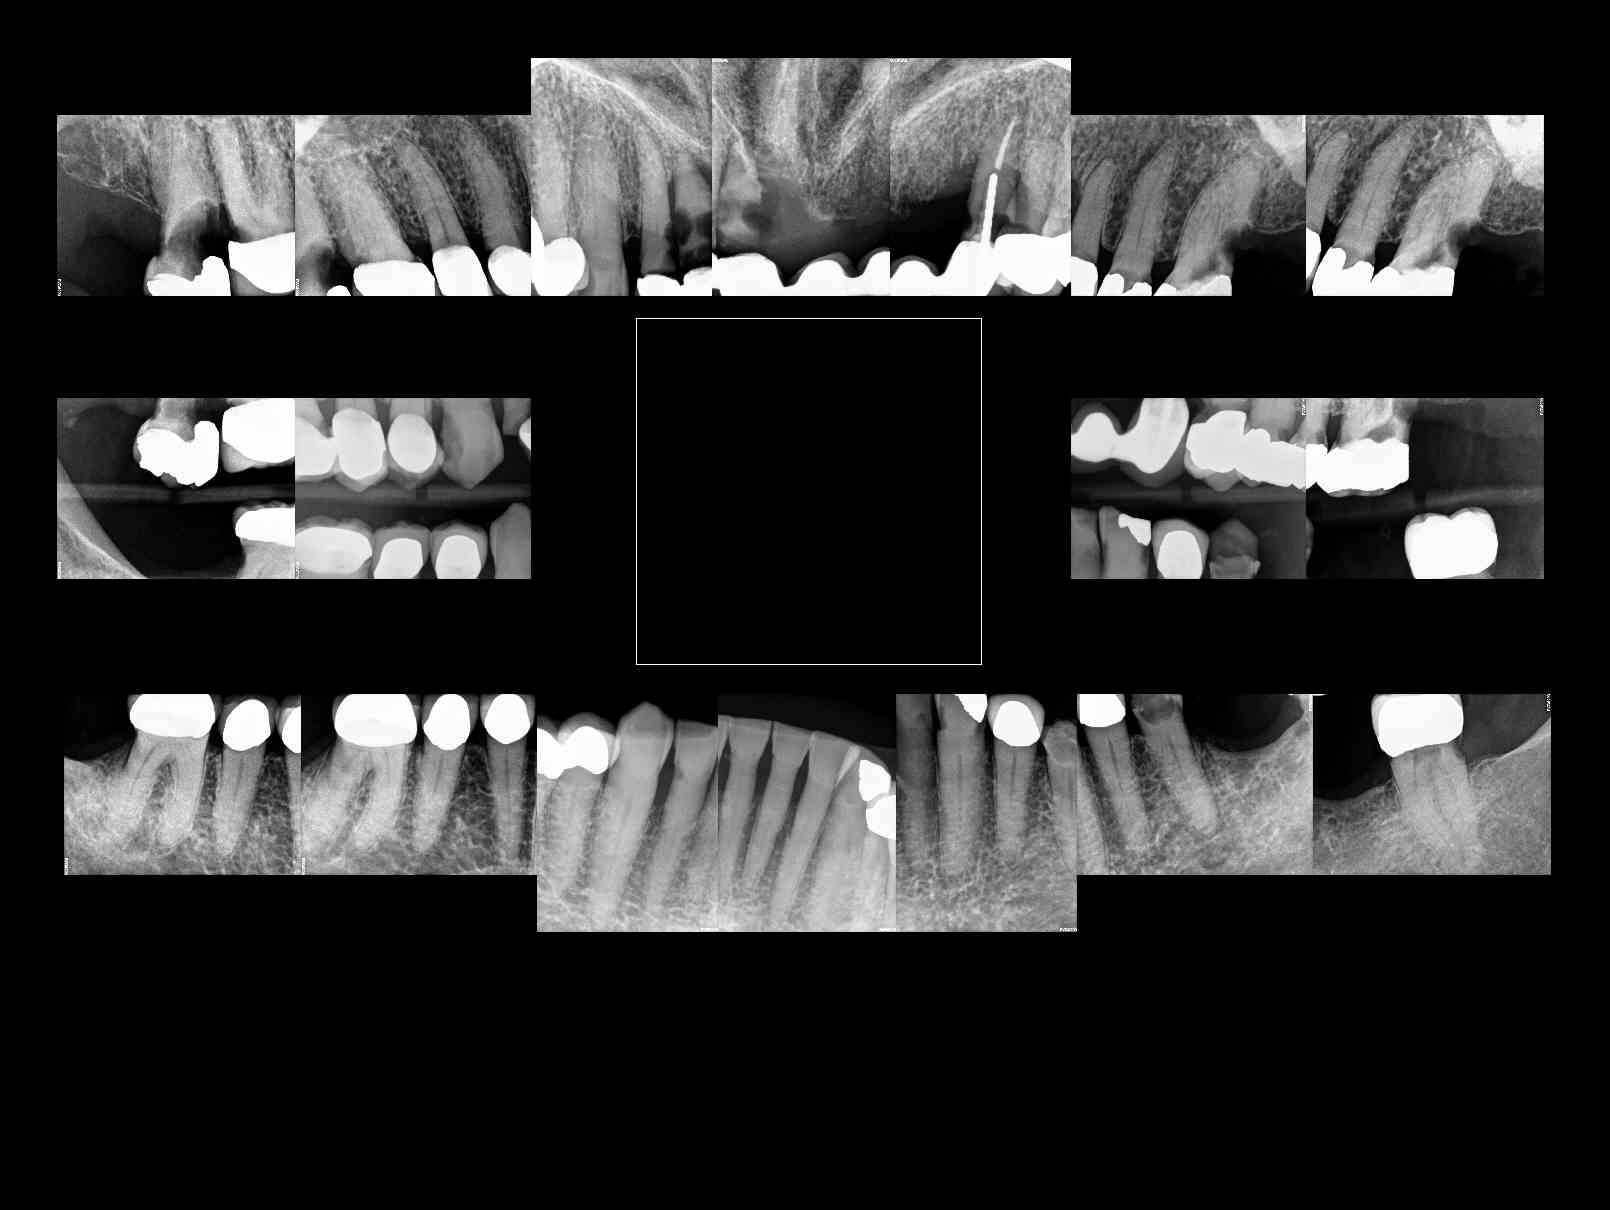

Patient requests ALL ON 4 for both upper and lower arches, complete case fee. X-rays available, taken last week